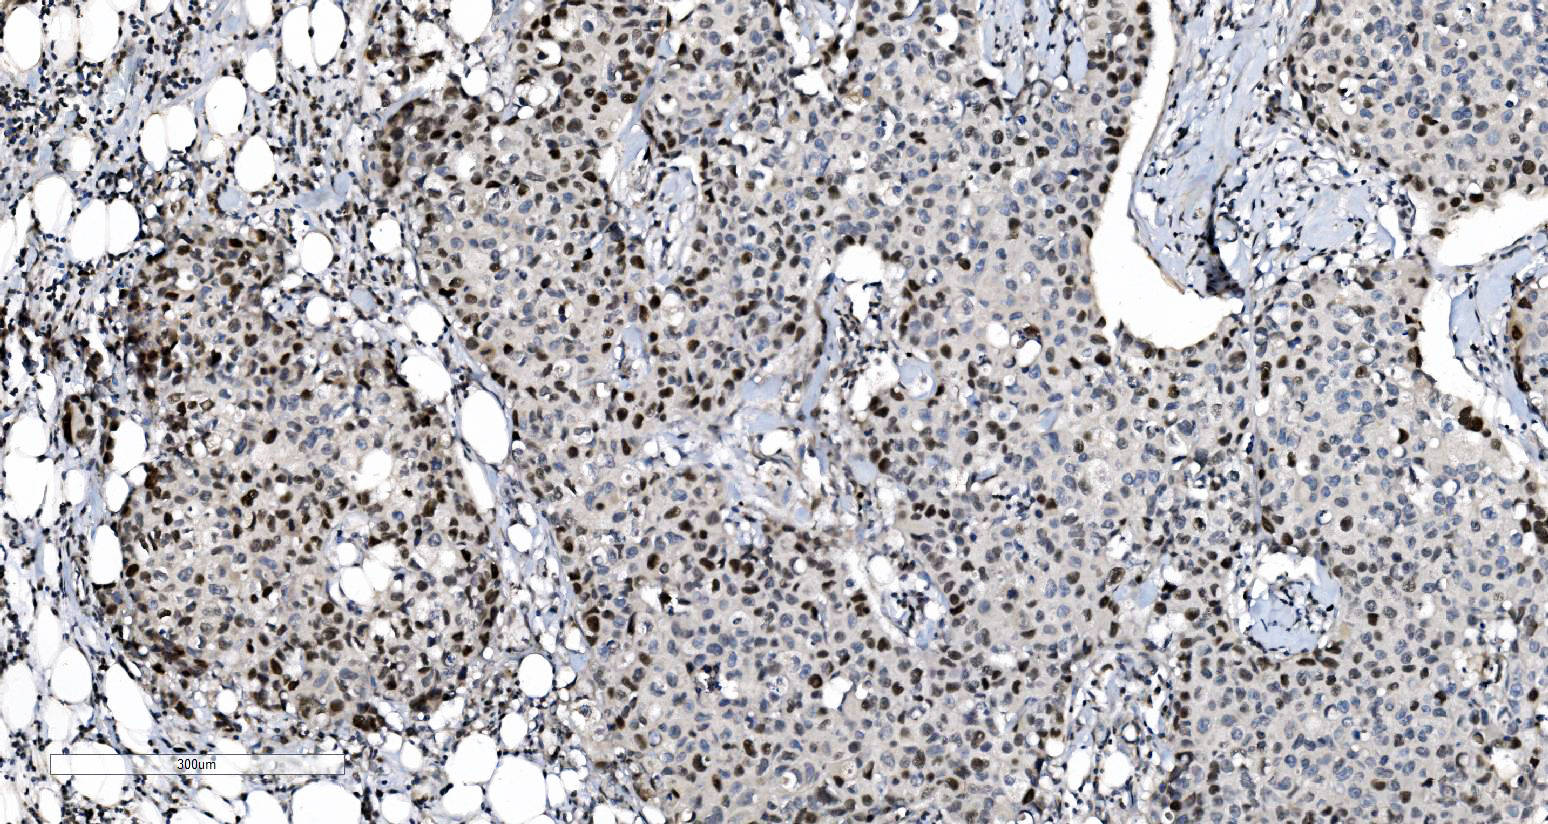

IHC analysis of MCM6 using anti-MCM6 antibody (M02755).

MCM6 was detected in a paraffin-embedded section of human gastric adenocarcinoma tissue. Biotinylated goat anti-mouse IgG was used as secondary antibody. The tissue section was incubated with mouse anti-MCM6 Antibody (M02755) at a dilution of 1:200 and developed using Strepavidin-Biotin-Complex (SABC) (Catalog # SA1021) with DAB (Catalog # AR1027) as the chromogen.